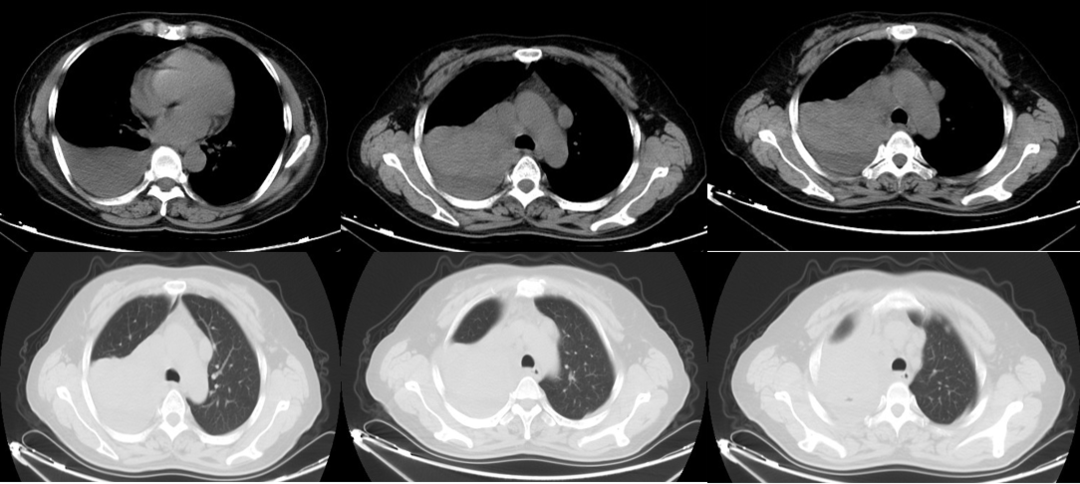

胸部CT(2020年12月6日):右肺中央型肺癌(肿瘤最大截面积7.2×5.2 cm)并右肺上叶肺转移、纵隔多发淋巴结转移CT表现、右侧胸腔积液,如图1-1所示。

图1-1 治疗基线胸部CT